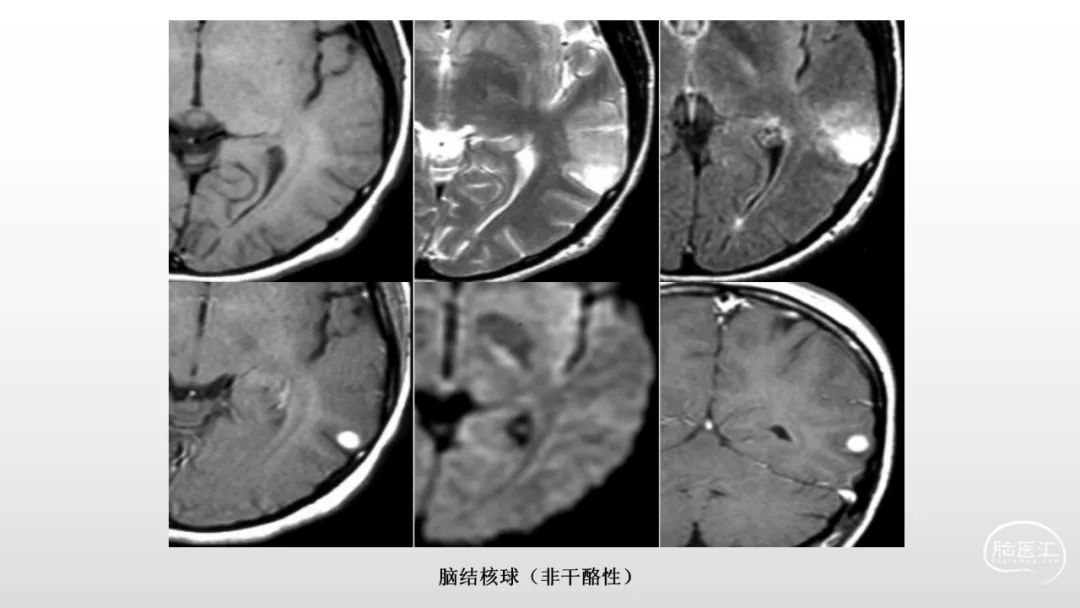

颅脑影像诊断基础知识讲座:感染和免疫性疾病1